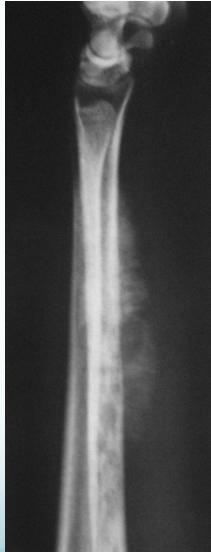

Radiological Features

- X-ray:

- Diaphyseal

- Bone destruction

- New bone formation:

- Along the bone

- “Onion-peel” layers

- ? “Sun-ray”

- ? Codman’s triangle

- Secondaries – in skeleton